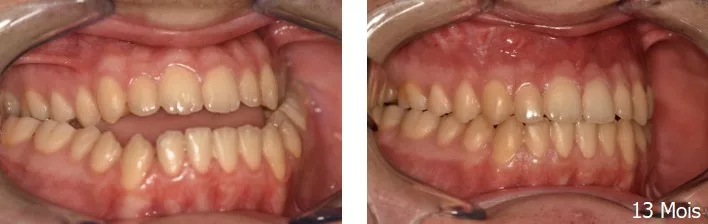

Chirurgie orthognathique

Classe III